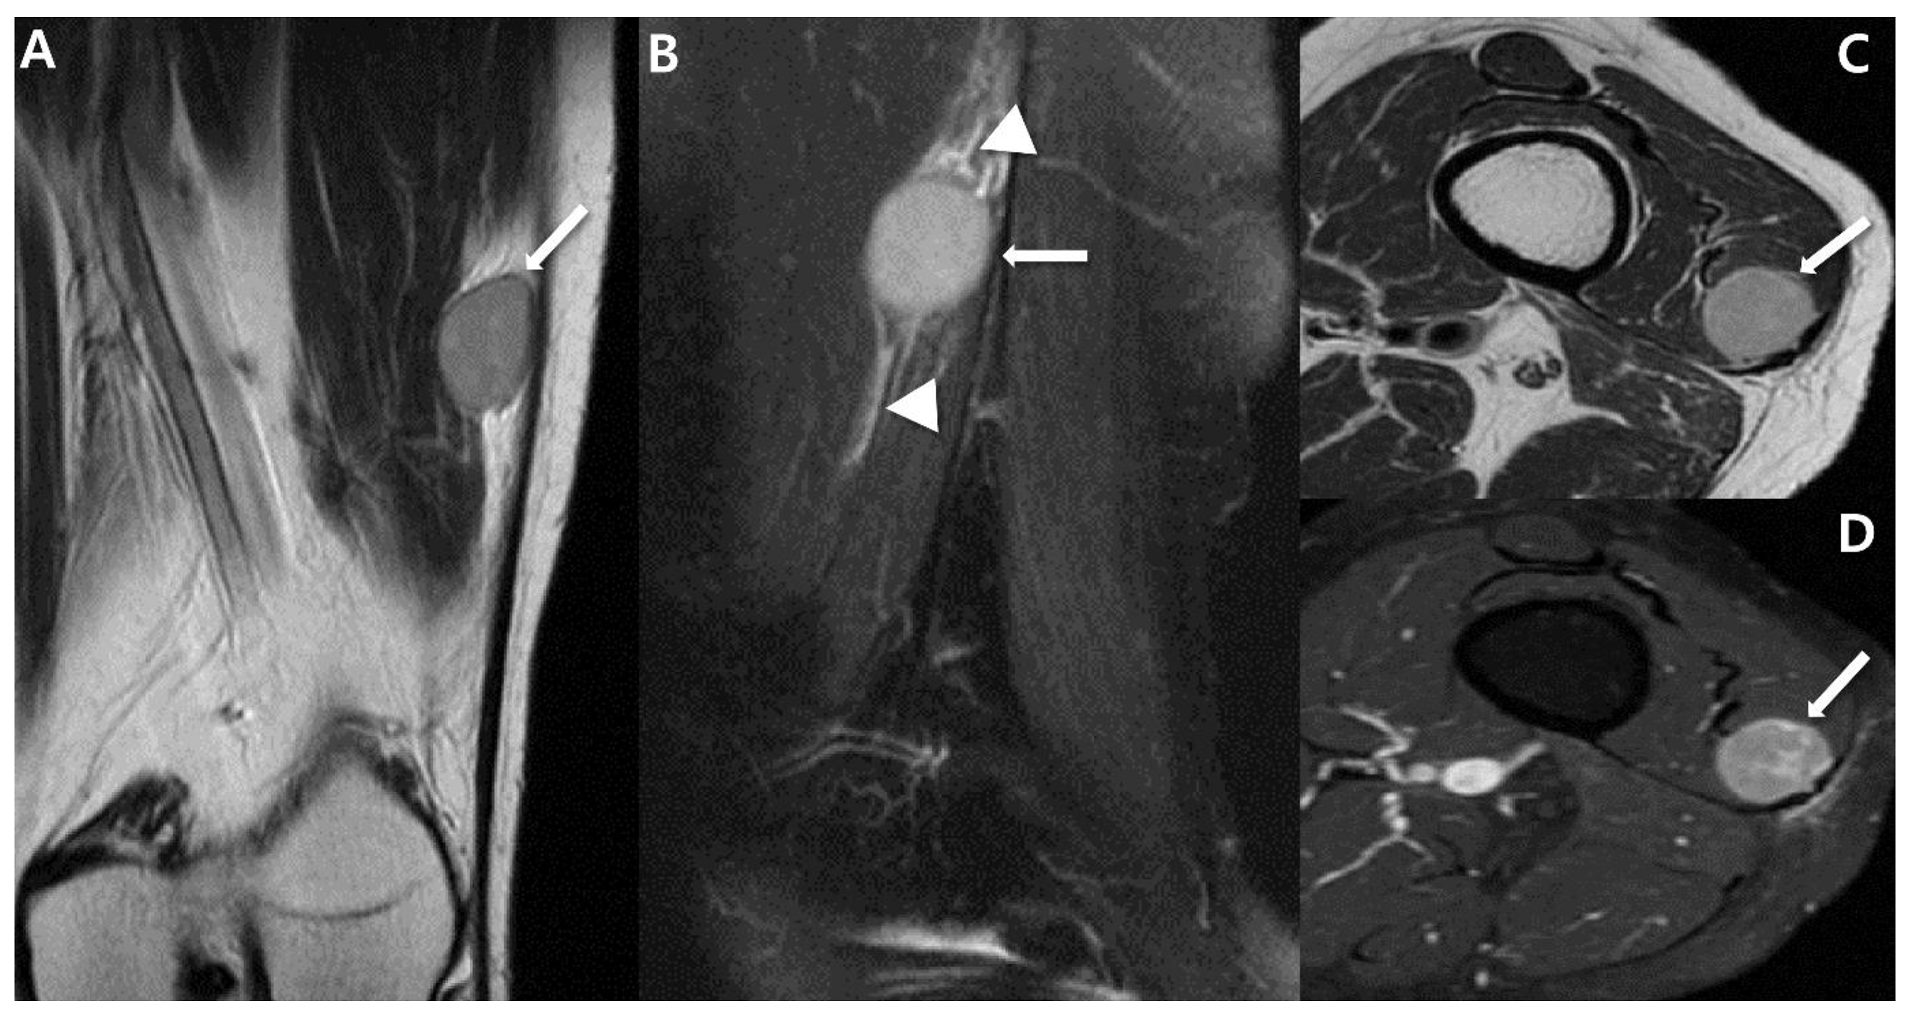

2.4. Magnetic Resonance Imaging (MRI)

3. Uncommon Primary Sites of Synovial Sarcoma in the Extremities

- Larque, A.B.; Bredella, M.A.; Nielsen, G.P.; Chebib, I. Synovial sarcoma mimicking benign peripheral nerve sheath tumor. Skelet. Radiol. 2017, 46, 1463–1468. [Google Scholar] [CrossRef]

- Scheithauer, B.W.; Amrami, K.K.; Folpe, A.L.; Silva, A.I.; Edgar, M.A.; Woodruff, J.M.; Levi, A.D.; Spinner, R.J. Synovial sarcoma of nerve. Hum. Pathol. 2011, 42, 568–577. [Google Scholar] [CrossRef]

- Hashimoto, K.; Nishimura, S.; Fujii, K.; Kakinoki, R.; Akagi, M. Intraneural synovial sarcoma of the tibial nerve. Rare Tumors 2018, 10, 2036361318776495. [Google Scholar] [CrossRef] [PubMed]

- Shahid, K.R.; Amrami, K.K.; Spinner, R.J. Primary monophasic synovial sarcoma presenting as a benign neurogenic tumor: Case review and review of the literature. J. Surg. Orthop. Adv. 2010, 19, 129–133. [Google Scholar] [PubMed]